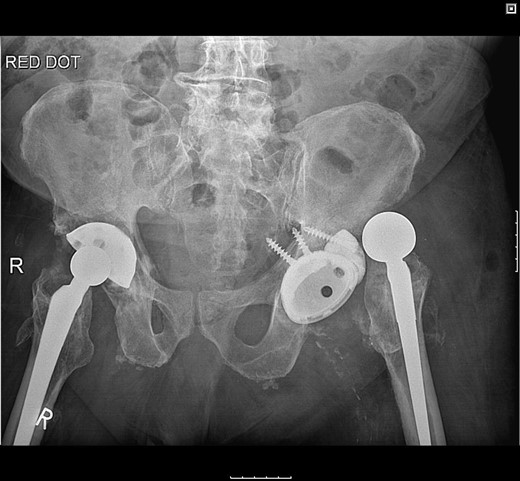

Postoperatively, the patient fell on the ward resulting in posterior dislocation (Fig. 5) requiring an open reduction. Subsequently, the patient developed a superficial surgical site infection, which resolved with antibiotic therapy. Three months following discharge, the patient was pain-free and could ambulate with a Zimmer frame.

Radiograph following postoperative fall demonstrating posterior dislocation.